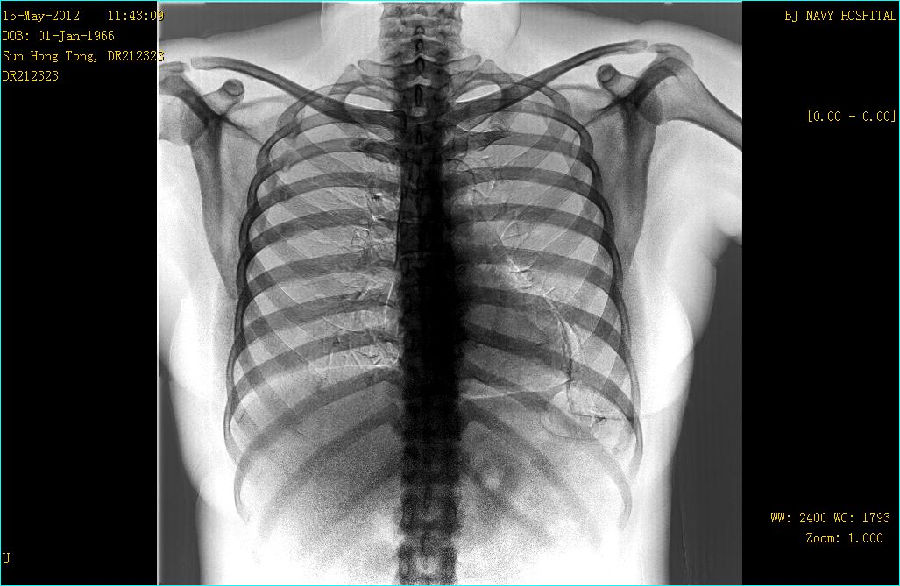

双能成像图片:

病例点评: GE公司的双能成像检查采用可以快速读取的X线平板探测器,由X射线球管间隔约150ms进行低能(低kVp)和高能(高kVp)两次曝光。采集到的图像经过图像工作站快速处理产生一组3幅图像:标准平面图像,软组织图像和骨骼(钙化)组织图像。这种双能量DR检查对于改善肋骨后面重叠区域的非钙化结节的能见度非常有效。同时对在肋骨间和超过骨组织钙化的结节能更好地显示。